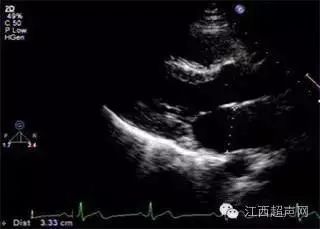

美国超声心动图协会指南建议应用四腔心切面于舒张中期测量二尖瓣环径(2)

舒张期分别测量)01美国超声心动图学会(ase)关于心腔定量分析的指南